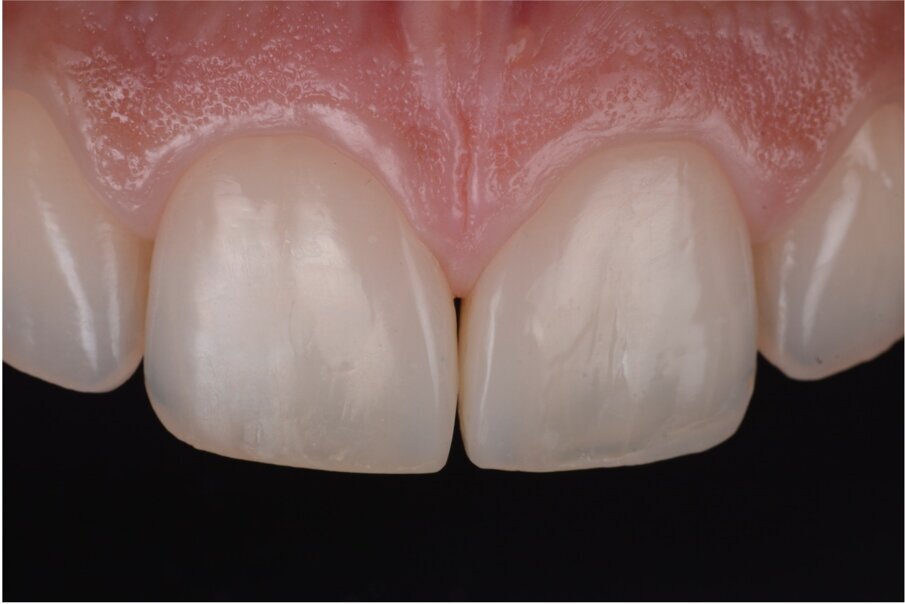

Fig. 2–4: Common troubles with a classic approach.

What were the associated problems with the older techniques including the one you used? The greatest problem for the freehand techniques, without a doubt, is the lack of cervical precision and the creation of overhangs. I have seen countless patients with bleeding gums that are not able to floss properly. Another common problem with the classical approach was the final shape. With a double emergence profile, it gave the final restoration an awkward shape (Figs. 2–4). Problems for direct diastema closure exclusively with matrices are the over contouring and the under contouring at the cervical level, discordant contact points, shifted proximal contacts, and massive excess production. To be honest, I have always been discouraged from trying that approach.